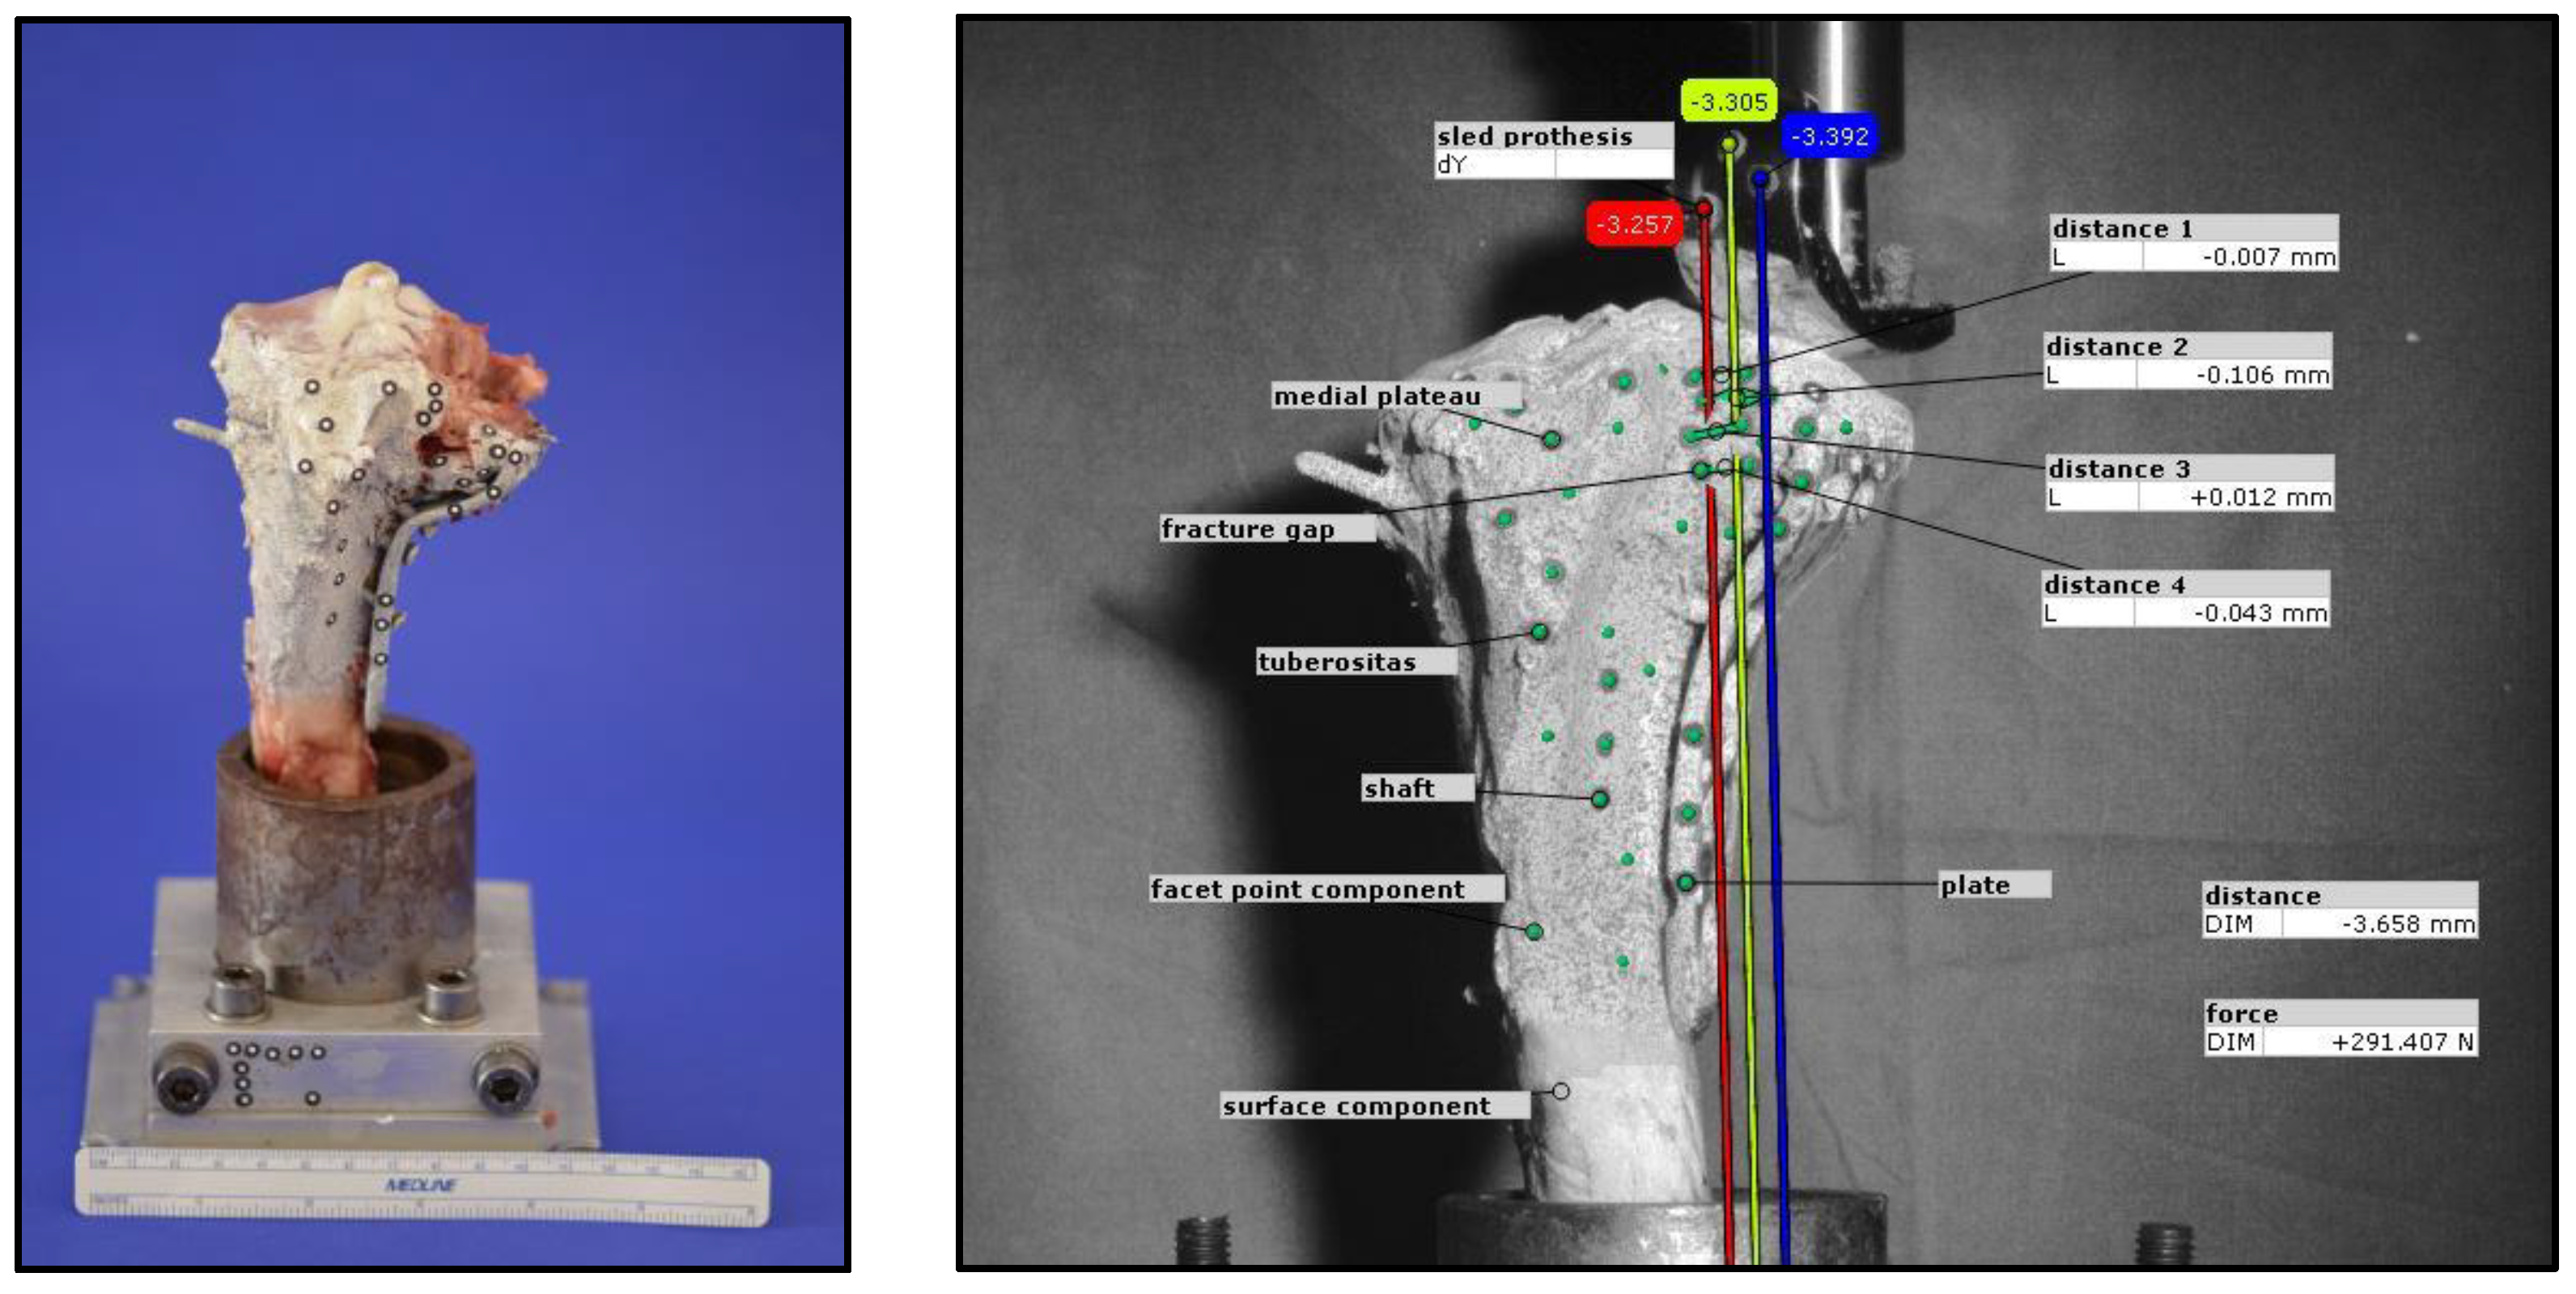

During optical data acquisition, every 20th cycle was recorded once the voltage exceeded 2.9 V, resulting in a total of 150 images captured during cyclic loading at 300 N. To analyze movement, self-adhesive markers were applied following a predefined pattern. Prior to marker placement, the bone was evenly coated with white paint to enhance strain measurement, followed by the application of fine black speckles to create a facet component for the optical system. The distance for evaluating the displacement was determined on 3 corresponding pairs of markers, medial and lateral to the fracture gap. For three-dimensional motion analysis, at least three markers per element were used, with four markers applied in certain cases (e.g., at the fracture gap) to improve detection accuracy. The analyzed elements included the prosthetic sled, medial plateau, fracture gaps, and fixation plate. Additional reference markers were placed on the test setup to establish a coordinate system.

The camera was positioned laterally to the bone to optimize visualization of the fracture gap. Displacement analysis focused on the y-axis movement of the prosthetic sled within the lateral fracture gap, which was compared to measurements from the materials testing machine. The total displacement at the end of testing was determined as the mean of three y-axis vectors. Furthermore, vertical displacements at four predefined locations within the fracture gap were evaluated. Representative examples illustrating the methodology are shown in Figure 4.

Figure 4. Exemplary test setup for analysis using an optical system.